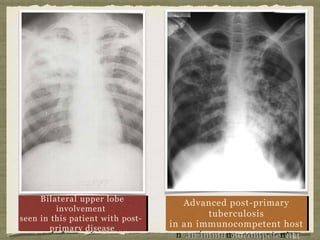

Bilateral upper lobe

seen in this patient with post-

Advanced post-primary

in an immunocompetent host